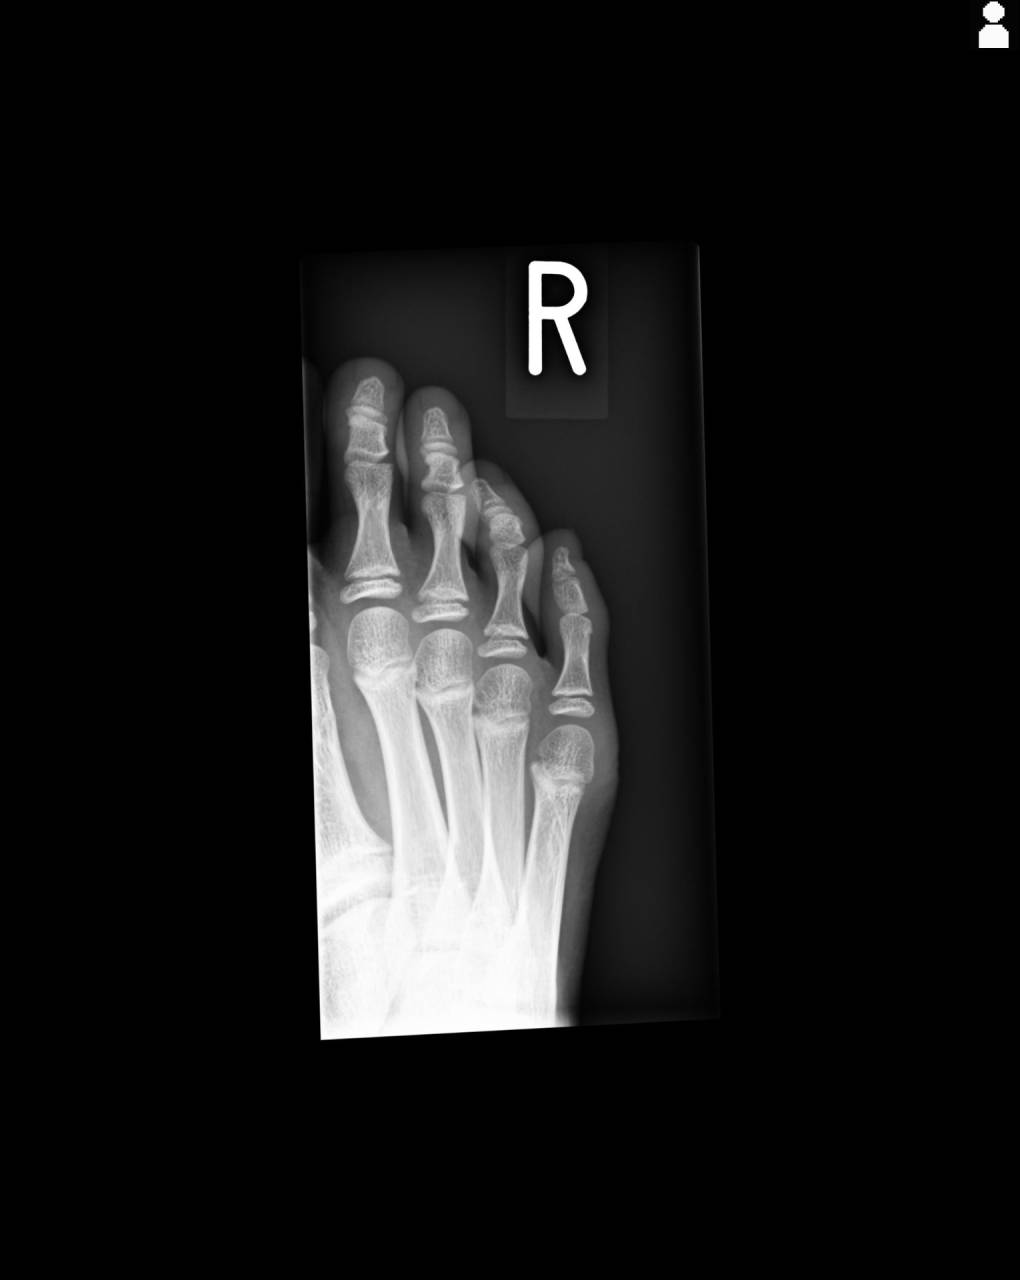

超音波観察装置(エコー)にて確認をしていくと中節骨骨頭に骨折線が確認できたので、骨折の疑いが濃厚になったので当整骨院が提携している病院にてレントゲン撮影を依頼しました。

撮影した画像を確認すると右第5趾中節骨骨頭に骨折が確認できたので骨折として施術を進めていきます。